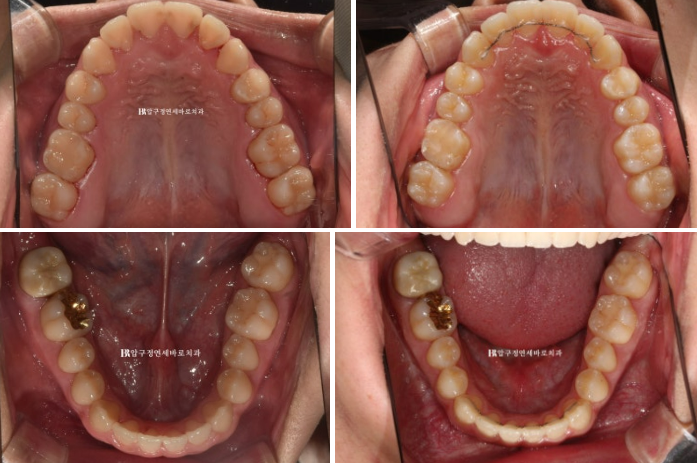

주걱턱 (3급 부정교합)에서는 상악 맨 뒤 큰 어금니가 대합치가 없어 내려와 있는 경우가 많습니다.

이 부분 해결을 위해 입천장에 교정용 나사 미니스크류를 심고 술전교정을 진행했습니다.

약 4개월의 술전교정 후 모습입니다.

23.12

내려와있던 위 맨 뒤 큰 어금니는 제 위치로 잘 올라갔고 양악수술을 위해서 철사로 고정을 해둡니다.